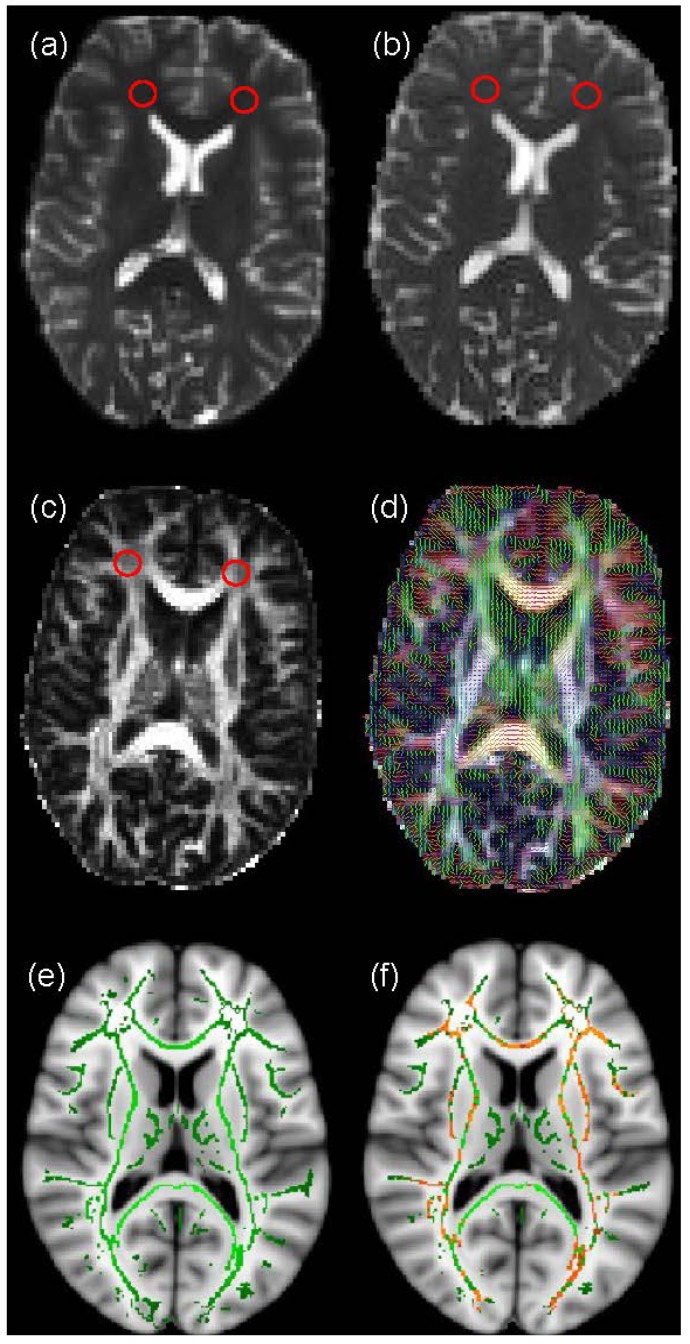

brainsci-04-00405-g001

“In recent years, musicians have been increasingly recruited to investigate grey and white matter neuroplasticity induced by skill acquisition. The development of Diffusion Tensor Magnetic Resonance Imaging (DT-MRI) has allowed more detailed investigation of white matter connections within the brain, addressing questions about the effect of musical training on connectivity between specific brain regions. Here, current DT-MRI analysis techniques are discussed and the available evidence from DT-MRI studies into differences in white matter architecture between musicians and non-musicians is reviewed. Collectively, the existing literature tends to support the hypothesis that musical training can induce changes in cross-hemispheric connections, with significant differences frequently reported in various regions of the corpus callosum of musicians compared with non-musicians. However, differences found in intra-hemispheric fibres have not always been replicated, while findings regarding the internal capsule and corticospinal tracts appear to be contradictory. There is also recent evidence to suggest that variances in white matter structure in non-musicians may correlate with their ability to learn musical skills, offering an alternative explanation for the structural differences observed between musicians and non-musicians. Considering the inconsistencies in the current literature, possible reasons for conflicting results are offered, along with suggestions for future research in this area.”